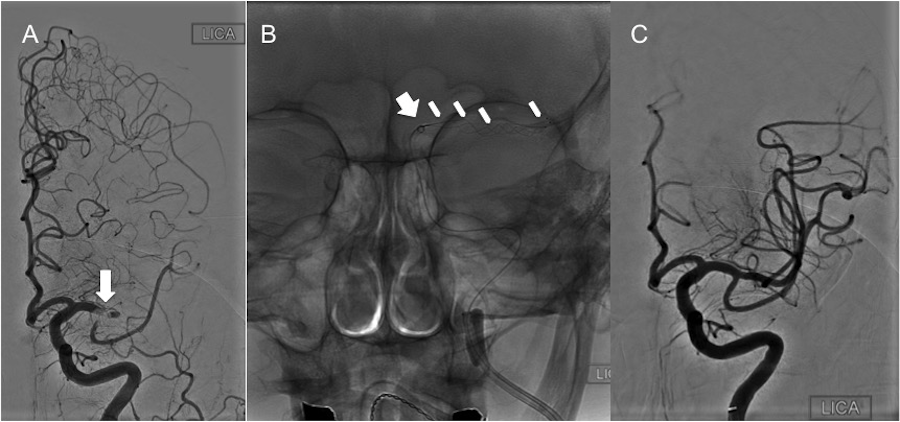

Case 3

A 91-year-old female, pre-stroke mRS of 1, presented with the acute onset of aphasia, right facial droop, and right hemiparesis, with an NIHSS of 23. She was a “wake-up” stroke and, thus, not a candidate for rtPA. A non-contrast CT of the head demonstrated an Alberta Stroke Program Early CT Score (ASPECTS) of 9 with subtle hypodensity in the left insular ribbon. A CTA of the head and neck demonstrated occlusion of the left M1 segment with limited collateral circulation. She was taken to the angiography suite for a thrombectomy under general anesthesia, as she was confused and agitated. The triaxial assembly included an 8 Fr FlowGate (Stryker Neurovascular) for BGC at the cervical left ICA, the Arc™ catheter (Medtronic) used as the intermediate AC, and a Trevo® Pro 18 microcatheter over a Synchro-2® microwire (Stryker Neurovascular). The cavernous carotid artery of this patient was a type IB (mild tortuosity) with open configuration/angles of the anterior and posterior genu, with the subcategory determined by the posterior genu angle, which, in her case, was equal to 90 degrees [10]. The horizontal segment of this patient’s cavernous carotid lacked any tortuosity. Angiographic runs determined that the clot was extending from the mid-left M1 to the left MCA bifurcation (Figure 3A). After traversing the clot with the microcatheter/microwire system, a Trevo® XP ProVue 4 x 20 mm stent-retriever (Stryker Neurovascular) was deployed (Figure 3B). With only a single thrombectomy pass, there was complete recanalization of the left MCA with a TICI 3 angiographic outcome (Figure 3C). The patient was extubated, and at about one hour after the procedure, her right upper mobility and strength were significantly improved. By POD 4, her NIHSS was down to 3, with some subtle dysarthria, right facial droop, and 4/5 strength in her right upper extremity.